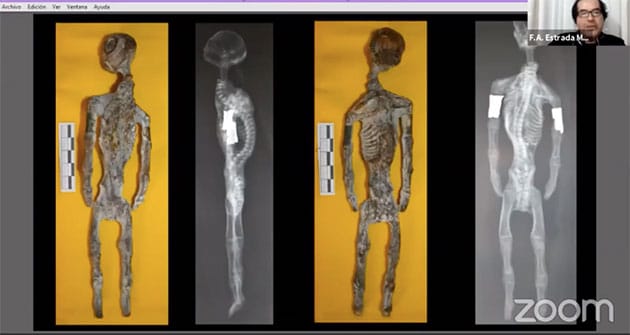

Schon zuvor hatte GreWi über die Übernahme der Funde und die Untersuchungen an der UNICA berichtet. Abschließend organisierten Studenten und Mitglieder der für diese Untersuchungen zuständigen archäologischen und forensisch-rechtsmedizinischen Fakultäten der UNICA verschiedene Online-Präsentationen und Konferenzen zu den Ergebnissen (weiterfühenden Links dazu finden Sie am Ende dieses Artikels). Unter dem bereits vielsagenden Titel „Anatomie eines Betrugs: Der Fall der mutmaßlichen dreifingerigen/dreizehigen humanoiden Reptilien-Mumien von Nazca“ präsentierte dann der Archäologe Flavio Antonio Estrada Moreno am 7. August 2020 via Zoom eine Zusammenfassung der eindeutigen Resultate.

Zu „Material und Methoden“ erläutert Estrada Moreno, dass hierzu Röntgenaufnahmen der besagten Mumien, ebenso wie Aspekte der vergleichenden Anatomie und Analysen mit Infrarot-Spektroskopie zum Einsatz kamen, mit der die Zusammensetzung von Material und Stoffen zerstörungsfrei und von außen durchgeführt werden kann.

Anhand der Röntgenaufnahme (Abb. 36) ist zu erkennen, dass dieses Wesen überhaupt keine Halswirbel oder sonstige Halsknochen besitzt. Zugleich gibt es aber auch keine Anzeichen für eine diesen Hals und damit den Kopf stützende Muskulatur. Eine weitere anatomische Katastrophe ist der Einbau der Oberschenkel, die wie Arme platziert wurden. Zudem verfügt das Wesen über keine wirklichen Gelenke. Mit Ausnahme des Schädels stammen auch hier alle Knochen von Menschen – in diesem Fall von noch nicht ausgewachsenen Menschen, da sich an den Knochen Wachstumslinien erkennen lassen. Anhand dieser Merkmale schließen die Wissenschaftler, dass der Mensch, dessen Knochen hier verwendet/missbraucht wurden, Ernährungsprobleme hatte.

Albertos Schädel (Abb. 37 l. weiß) ist ähnlich gearbeitet, wie die vorigen Schädel der anderen kleinen Mumien (Abb. 37. r. blau), besteht selbst aber fast ausschließlich aus einem sogenannten Gehirnschädel (Neurokranium), der das Gehirn umschließt. Es finden sich keine weiteren Schädelteile. Die Röntgenaufnahmen (37) zeigt das anschaulich. Erneut vermuten die UNICA-Wissenschaftler, dass die weiße pudrige Farbe auf den Mumien oberflächlich offenkundige Fehler verdecken sollte.

Gemeinsam mit Alberto gelangte eine weitere Mumie an die Universität, die zuvor im Besitz von Gaia war und dort mit den Namen „Josefina“ bezeichnet wurde (Abb. 39, 40). Auch Josefina teilt nahezu alle Merkmale der anderen kleinen Mumien (siehe Kopf-Vergleich in Abb. 39) und Hände (Abb. 40, 41).

Aus den Röntgenaufnahmen geht ebenso hervor, dass auch diese Mumie keine wirklich funktionalen Gelenke besitzt. Mit dieser Anatomie hätte sich ein solches Wesen kaum bewegen können, da Knochen teilweise direkt aufeinanderstoßen, abgeschnitten und aufeinander gekantet wurden. Zudem ist ein Bein wesentlich länger als das andere.

Auch ein Vergleich von Josefinas Schädel (s. Abb. 44, 45, 46 l.) mit vorigen Schädeln (Abb. 44. 45, 46 r.) zeigt die Ähnlichkeiten und offenbart erneut, dass auch hier der umgedrehte Schädel eines Vierbeiners verwendet wurde. Auf den Schädeln sind linienförmige Grate zu erkennen (Abb. 47), an denen in der Natur bei den Tieren Muskeln ansetzten – Muskeln, für die es bei Josefina (und den anderen Mumienschädeln) aber keine Anzeichen gibt.